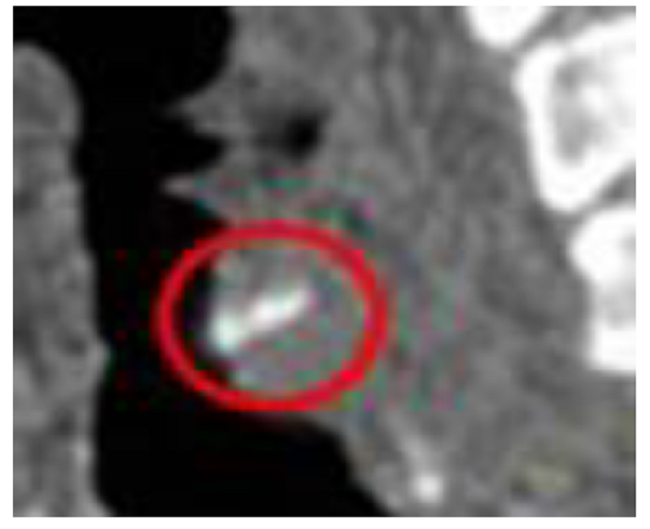

Se consultó el caso con especialistas en Otorrinolaringología, quienes concordaron con la existencia de un cuerpo extraño vegetal o con poco contenido de calcio, debido a que los estudios previos fueron negativos, por lo cual sugirieron realizar exámenes no convencionales como la resonancia magnética (Fig.1) y la endoscopia de vías aéreas (Fig.2), que finalmente permitieron visualizar el cuerpo extraño. Se trataba de una espina de pescado localizada en la región cricofaríngea.